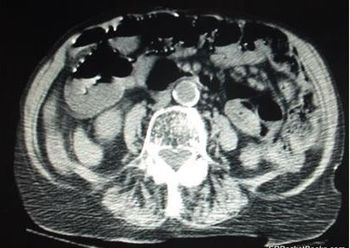

Symptoms have been present for 2 days. Lab studies are notable for BUN (43 mg/dL) and CO2 (21 mmol/L). The real problem is visible on CT of the abdomen and pelvis. Your diagnosis?

At risk for mesenteric ischemia-an uncommon but feared cause of abdominal pain-are the elderly and chronically ill.